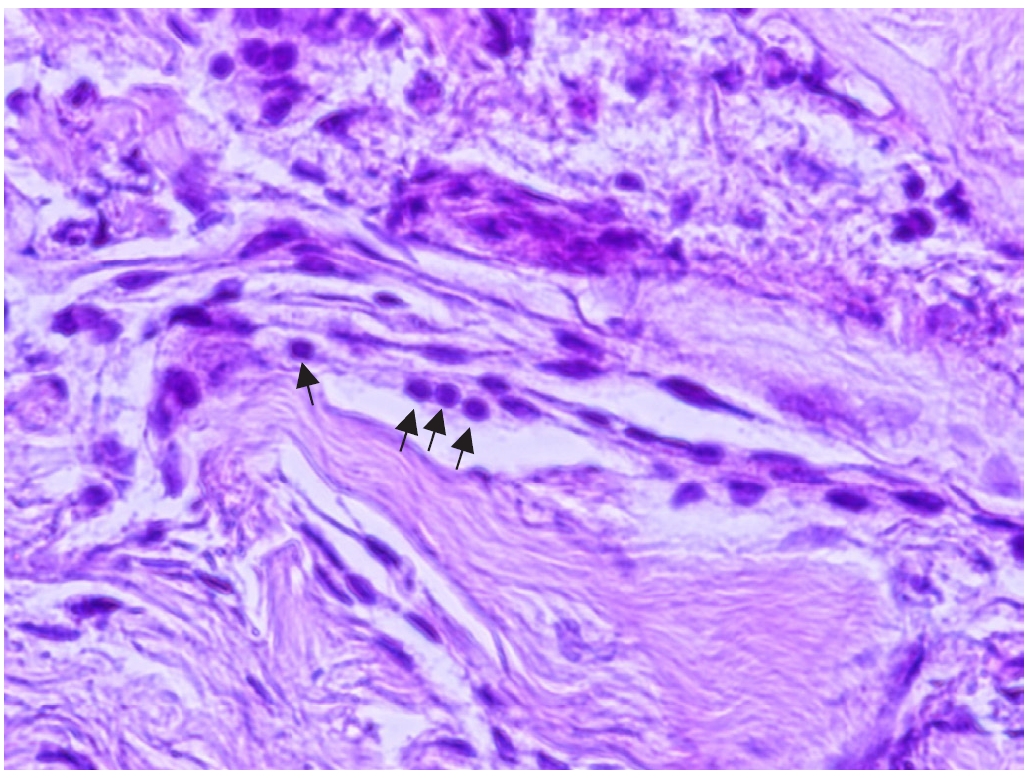

Histopathological examination revealed irregular, multilayered fibrous structures accompanied by numerous calcareous corpuscles (

Fig. 5). This study was approved by the Institutional Review Board of Jeju National University Hospital (JEJUNUH 2026-01-037) and informed consent was waived.

Microscopic examination showed irregular, multilayered fibrous structures accompanied by numerous calcareous corpuscles, which were histologically distinct from the racemose form. Calcareous corpuscles are well recognized as important histological markers of cestode tissue [

11].

Fig. 5.Microscopic examination revealed an irregular, multifold, fibrous-like layer, and numerous calcareous corpuscles were observed (×200). Hematoxylin-eosin staining was used and arrows indicate calcareous corpuscles.